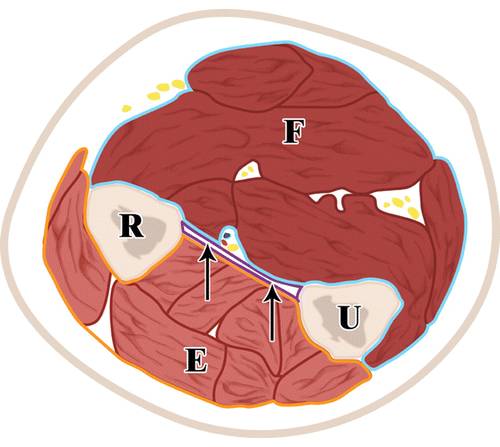

![]()

4/前臂在轴向平面上的示意图。

骨间膜(箭头)分隔伸肌(E)和屈肌(F)隔间。应特别小心不要伤及骨间膜,从而避免多个隔室的污染。R =桡骨,U =尺骨。